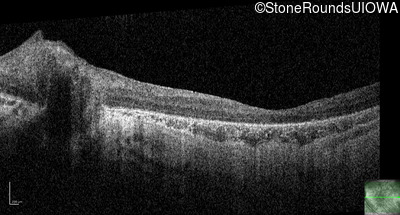

Optical Coherence Tomography - Left - 20/500 sc

Exemplar / OCT Stack